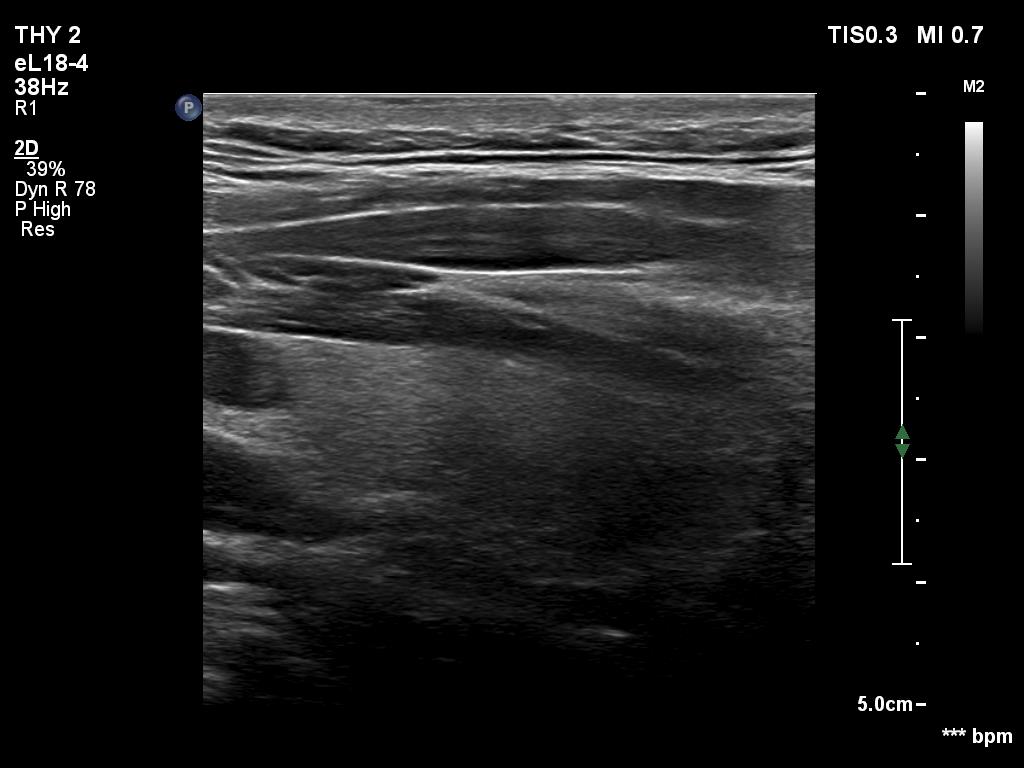

Ultrasonography. The thyroid was echonormal and had two cystic lesions in the left lobe. With higher frequency, the dorsal part of both lobes presented with hypoechoic blurred areas. With frequency decreased, these areas have disappeared.

Comment. This case illustrated the well-known inverse relation between penetrance and resolution. Better the former worst the latter and conversely. This has particular and practical importance if we examine obese patients using high-end equipment with high frequency. In such patients the obesity can significantly worsen the penetrance. This can be solved by decreasing the frequency and remove all software harmonization.